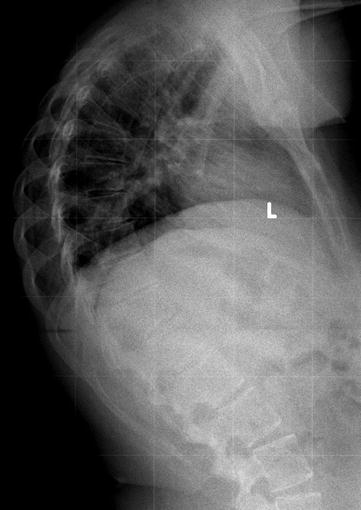

Scheuermann's Disease Schmorl's Node. In 1964, sorensen introduced the classic diagnostic criteria for sd of three consecutive vertebral bodies with anterior wedging of at least 5 degrees.5 additional imaging findings include endplate irregularities, commonly manifested as schmorl's nodes. Small disc herniations through the endplates of the vertebrae (called schmorl's nodes). Scheuermann's disease (also called scheuermann's kyphosis) is a condition that starts in childhood. The diagnosis is usually made on plain film. Scheuermann's disease is a juvenile osteochondrosis of the spine. Descriptions of schmorl's nodes note they generally do not cause many problems and they are in fact a pretty common side effect of general wear and tear on the spine. The radiographic aspects are related to the vertebral endplate lesions and include vertebral wedging, irregularity of the vertebral endplate, and schmorl's node (intraossous disk herniation). The upper and middle areas of the spine, called the thoracic spine, consist of the 12 vertebrae below the seven that make up the cervical spine. Scheuermann's disease is a developmental disorder of the spine that is caused by abnormal growth of the vertebrae. When scheuermann's disease is present, the thoracic area of the spine is overly curved from the side. Scheuermann's disease describes a condition where the vertebrae grow unevenly with respect to the sagittal plane; Scheuermann's disease is a congenital condition that causes curvature of the spine in teenagers. Scheuermann disease, also known as juvenile kyphosis, juvenile discogenic disease 11, or vertebral epiphysitis, is a common condition which results in kyphosis of the thoracic or thoracolumbar spine. It affects less than one percent of the population and occurs mostly in children between the ages of 10 this forms pockets of disc material inside the vertebral body, a condition called schmorl's nodes. Range of motion:the physician assesses the degree to which the patient can bend forward, back, and side to side.

Scheuermann disease | Radiology Case | Radiopaedia.org. Scheuermann's disease (also called scheuermann's kyphosis) is a condition that starts in childhood. In 1964, sorensen introduced the classic diagnostic criteria for sd of three consecutive vertebral bodies with anterior wedging of at least 5 degrees.5 additional imaging findings include endplate irregularities, commonly manifested as schmorl's nodes. The upper and middle areas of the spine, called the thoracic spine, consist of the 12 vertebrae below the seven that make up the cervical spine. Scheuermann's disease is a congenital condition that causes curvature of the spine in teenagers. Small disc herniations through the endplates of the vertebrae (called schmorl's nodes). Descriptions of schmorl's nodes note they generally do not cause many problems and they are in fact a pretty common side effect of general wear and tear on the spine. Scheuermann's disease is a juvenile osteochondrosis of the spine. The diagnosis is usually made on plain film. Scheuermann's disease describes a condition where the vertebrae grow unevenly with respect to the sagittal plane; Scheuermann's disease is a developmental disorder of the spine that is caused by abnormal growth of the vertebrae. Scheuermann disease, also known as juvenile kyphosis, juvenile discogenic disease 11, or vertebral epiphysitis, is a common condition which results in kyphosis of the thoracic or thoracolumbar spine. Range of motion:the physician assesses the degree to which the patient can bend forward, back, and side to side. It affects less than one percent of the population and occurs mostly in children between the ages of 10 this forms pockets of disc material inside the vertebral body, a condition called schmorl's nodes. The radiographic aspects are related to the vertebral endplate lesions and include vertebral wedging, irregularity of the vertebral endplate, and schmorl's node (intraossous disk herniation). When scheuermann's disease is present, the thoracic area of the spine is overly curved from the side.

With the help of some of the bravest and strongest people in the world, we, at the scheuermann's disease fund, have created a video project to let people know what it is like to live with scheuermann's disease, especially as we. These nodes are areas where the disc (cushion) between each vertebra pushes through the bone at the bottom and the top of the vertebra. Range of motion:the physician assesses the degree to which the patient can bend forward, back, and side to side. Mri dorso lumbar region spine sagittal t2w images show: Scheuermann kyphosis, also known as scheuermann disease, juvenile kyphosis or juvenile discogenic disease, is a condition of. Scheuermann's disease describes a condition where the vertebrae grow unevenly with respect to the sagittal plane; Schmorl's nodes (each marked by a white asterisk) are seen as multiple areas where disk material extrudes through the endplate in the lumbar region. The diagnosis is usually made on plain film. This commonly results in back pain and is usually managed medically. In 1964, sorensen introduced the classic diagnostic criteria for sd of three consecutive vertebral bodies with anterior wedging of at least 5 degrees.5 additional imaging findings include endplate irregularities, commonly manifested as schmorl's nodes. Scheuermann's disease (also called scheuermann's kyphosis) is a condition that starts in childhood. Scheuermann's disease is differentiated by a 5o or more angle of the vertebral body viewed laterally via radiographs.3,5 in addition there may a thicknening, undulence, schmorl nodes, and a cobb angle greater than 40o.3,5 individuals with sd typically have excessively protracted scapula. Scheuermann disease, also known as juvenile kyphosis, juvenile discogenic disease 11, or vertebral epiphysitis, is a common condition which results in kyphosis of the thoracic or thoracolumbar spine. All had various disk problems including scheuermann's disease, schmorl's nodes and limbus vertebrae. For most patients, scheuermann's disease runs a fairly benign course, with resolution of symptoms at skeletal maturity. Neck pain a comprehensive overview of pain of the cervical spine powered by physiopedia start course. Mri findings in 12 patients}. Small disc herniations through the endplates of the vertebrae (called schmorl's nodes). Scheuermann's disease, schmorl's nodes, and the limbus vertebra: However, scheuermann's disease is still generally considered as a hereditary disorder of unknown etiology 23. When scheuermann's disease is present, the thoracic area of the spine is overly curved from the side. Most can form after a heavy loading incident or trauma which forces the nucleus part of the disc through the endplate instead of the outer part of the disc. Multiple and contiguous involvement of vertebral bodies, the anterior wedging, antero posterior elongation, associated schmorl's nodes, end plate irregularity and disc space narrowing. Associated with irregular vertebral endplates, schmorl nodes, and loss of disc space height noted on sagittal imaging studies. Related online courses on physioplus. How do you get schmorl's nodes? Scheuermann, or scheuermann's, disease (juvenile kyphosis) is a deformity in the thoracic or thoracolumbar spine in which pediatric patients have an increased kyphosis along with backache and localized changes in the vertebral bodies. With scheuermann's disease, an abnormality causes parts of the vertebrae to grow at different rates during a child's growth spurt. Scheuermann's disease is a juvenile osteochondrosis of the spine. Schmorl's nodes and modic changes (endplate mri signal change) on lumbar mri, back pain and physical function restrictions seem to be more prevalent among patients with scheuermann's disease. It affects less than one percent of the population and occurs mostly in children between the ages of 10 this forms pockets of disc material inside the vertebral body, a condition called schmorl's nodes.